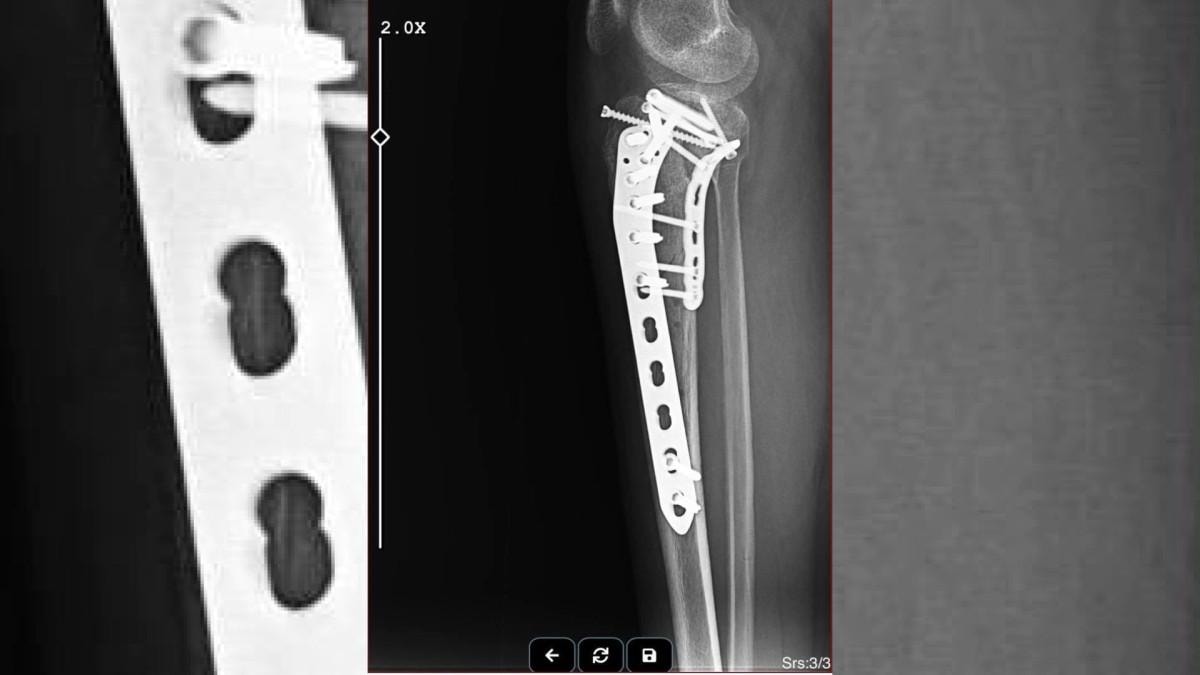

Bacağımda platinler mevcut, kaybettiğim belli başlı dokular oldu. Bu süreç psikolojik olarak tabii ki beni çok etkiledi. Sağlık problemlerim hala devam ediyor, tedavi sürecim hala devam ediyor. Burada asıl olay, yapılan saldırının mesleğe karşı, bir avukata ve bir kadına yapılmış olmasıydı." dedi.